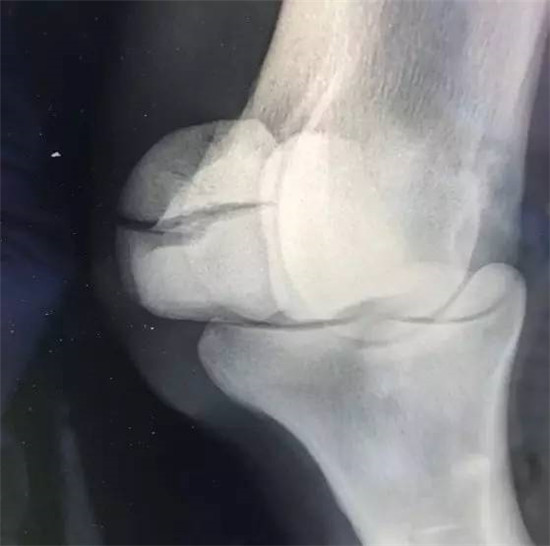

▲X光拍摄马匹球节部位

▲正常近端籽骨侧位图

▲“巨鹰拍翼”近端籽骨骨折斜位图,可发现近端籽骨明显裂开。图片来源Racing UK。